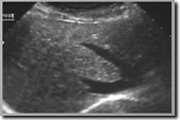

Met behulp van de echografie kan men elk weefsel onderzoeken in het lichaam op voorwaarde dat het niet is "verborgen" achter bot of bijvoorbeeld lucht. Het belangrijkste voordeel van echografie is dat het niet invasief is. Het doet in principe geen pijn.

Om vochthoudende collecties op te sporen (vbn. cyste,

bloeding,...) |

Ter beoordeling van de vorm en grote van de inwendige

organen

(vbn. milt, lever, pancreas, nieren, appendix,...) |